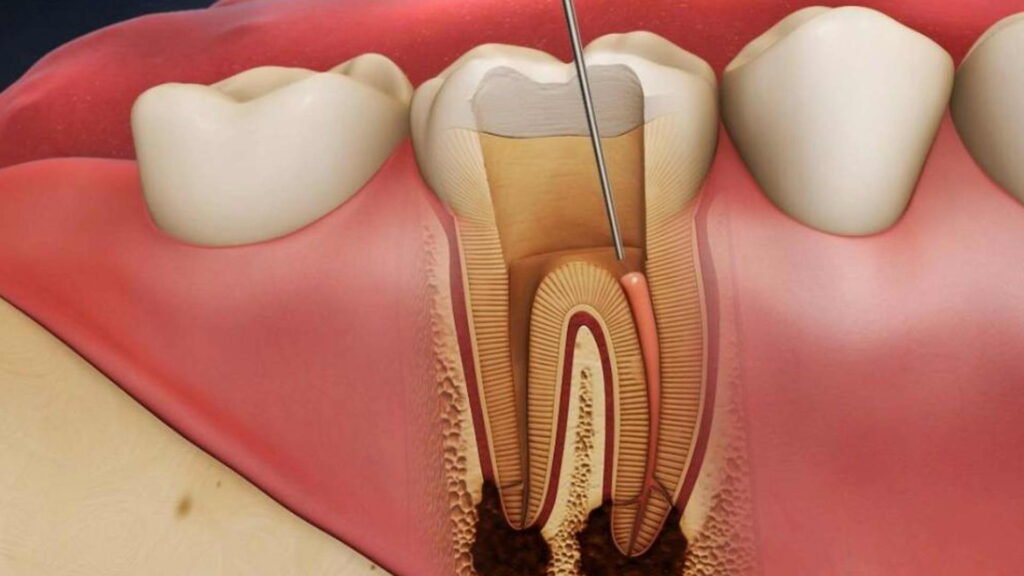

Endodontics is a branch of dentistry that deals with the interior of the tooth, particularly the dental pulp, which contains nerves, blood vessels, and connective tissue. Common endodontic treatments include root canal therapy, which is essential for saving teeth that might otherwise need to be extracted due to infection or damage.

Treatment Procedure: During a root canal procedure, we carefully remove the infected or damaged pulp from the tooth. The interior of the tooth is then cleaned, disinfected, and shaped to prepare it for filling. We use state-of-the-art technology and techniques to ensure precision and minimize discomfort.

Filling and Sealing: Once the tooth is prepared, we fill the cleaned root canals with a biocompatible material and seal them to prevent future infections. The treated tooth is then restored with a crown or filling to ensure it functions like a natural tooth.